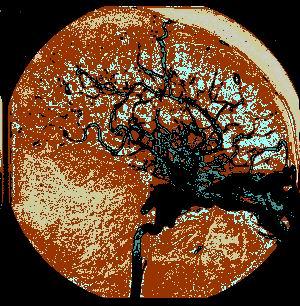

问题 病历摘要:??患者女性,25岁。10日前因车祸致头部外伤,伤后有短暂昏迷史,右鼻腔少量血性液体流出。8日前开始感颅内有杂音。7日前右眼睑出现肿胀伴右眼视力下降,并逐渐加重。既往体健。体检:神志清楚,右眼明显突出并有搏动,右眼睑及球结膜水肿充血,眼球部及颞部可听到与脉搏一致的隆隆样杂音。瞳孔右大于左(5:3mm),视力右眼失明,右眼球各方向运动均受限,左眼视力及运动正常。 根据造影结果,海绵窦内的血液通过下列哪些血管引流?提示:脑血管造影确诊为右颈内动脉海绵窦瘘

选项 A.眼静脉 B.蝶顶窦 C.外侧裂静脉 D.基底静脉 E.岩上窦 F.岩下窦 G.基底丛 H.翼丛

答案 AEF